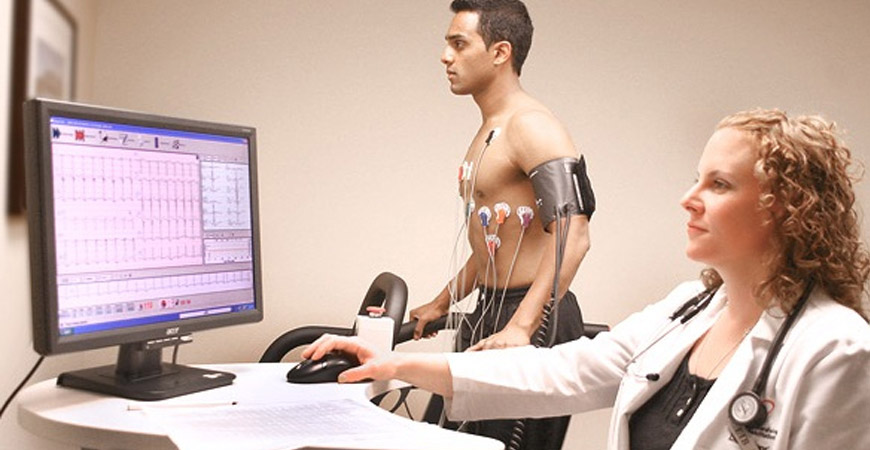

Computerised Stress Test